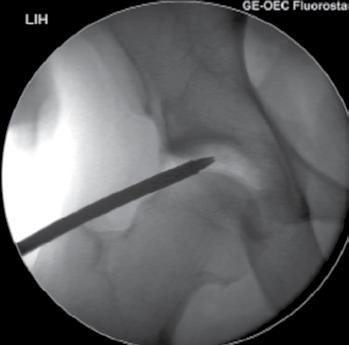

a. Vad är en s k CAM-lesion? (1p)

b. Vilka symtom kan en patient ha med en sådan lesion? (1p)

c. Vilka är de röntgenologiska undersökningsfynden? (1p)

a. CAM-lesion kan vara en orsak till femuroacetabulär impingement (FAI) där man har en påbyggnad på collum femoris främre övre omfång.

b. Symtom kan vara höftsmärta och inskränkt rörlighet, ssk flexion men även inåtrotation och adduktion.

c. På slätröntgen eller CT, alternativt MR ses ”Pistol-grepps-deformitet”, benpåbyggnad vid övergång superiort mellan caput-collum och förlust av sfäriciteten av caput femoris.